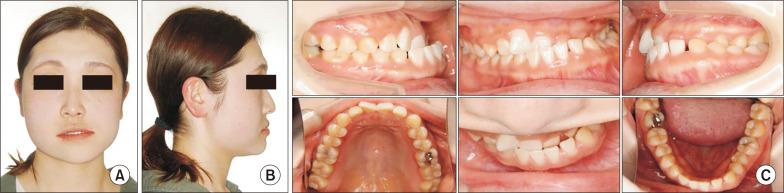

In patients with unilateral mandibular condyle hyperplasia, whether to perform condylectomy and orthognathic surgical procedures at the same time or orthognathic surgery in two stages for remains controversial. Reported here is a case of facial asymmetry with mandibular condyle hyperplasia, for which condylectomy and orthognathic surgery procedures were performed at the same time. A 28-year-old woman was presented to our department with chief complaints of left deviation of the mandible and right temporomandibular joint (TMJ) noise. Findings obtained in several imaging examinations led to a diagnosis of facial asymmetry associated with right mandibular condyle hyperplasia. Following 3 months of preoperative orthodontic treatment, in October 2018 under general anesthesia the patient underwent a right mandibular condylectomy, Le Fort I osteotomy, right mandibular sagittal split ramus osteotomy, and left mandibular inverted L ramus osteotomy. In examinations up to 3 years after surgery, good results were noted. For this case of severe facial asymmetry with mandibular condyle hyperplasia, early surgery and condylectomy were performed simultaneously to significantly shorten the total treatment time. The effectiveness of a surgery-early approach was confirmed by no postoperative findings indicating abnormalities in the TMJ or retroversion.

对于单侧下颌髁突增生的患者,是同期进行髁突切除术和正颌外科手术,还是分两阶段进行正颌手术,目前仍存在争议。本文报道了一例下颌髁突增生导致面部不对称的病例,该病例同期进行了髁突切除术和正颌外科手术。一名28岁女性因下颌向左偏斜及右侧颞下颌关节(TMJ)弹响为主诉前来我院就诊。多项影像学检查结果诊断为与右侧下颌髁突增生相关的面部不对称。经过3个月的术前正畸治疗后,2018年10月患者在全身麻醉下接受了右侧下颌髁突切除术、Le Fort I型截骨术、右侧下颌矢状劈开升支截骨术和左侧下颌倒L形升支截骨术。在术后长达3年的检查中,结果良好。对于这例严重的下颌髁突增生导致面部不对称的病例,早期进行手术并同期进行髁突切除术,显著缩短了总治疗时间。术后未发现TMJ异常或后倾等异常情况,证实了早期手术方法的有效性。